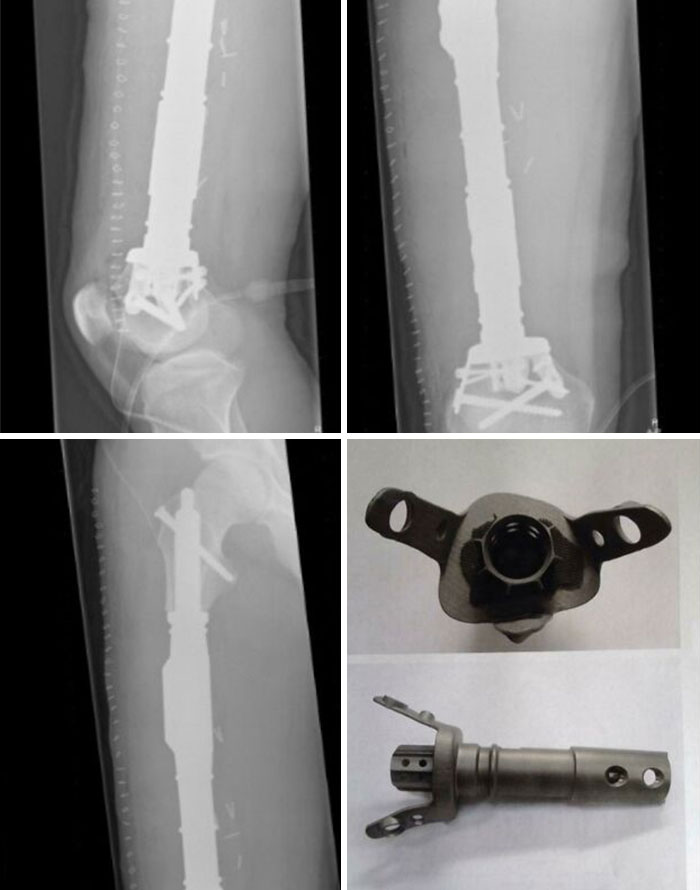

According To My Doctor I Was The First Person In The World To Receive A 3D Printed Bone In 2014. Without It, I Would Have Lost My Knee